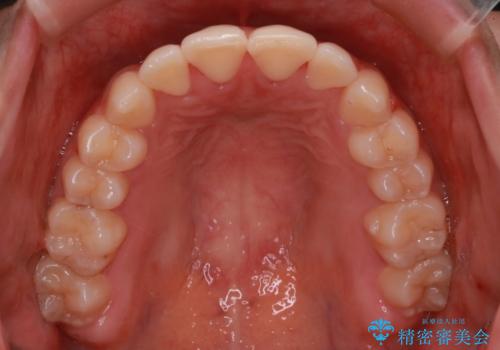

抜かない矯正 審美装置によるワイヤー治療

- 前歯のガタガタを主訴に来院されました。

装着時間に不安がある人は、ワイヤー矯正をおすすめしております。短期間で治療でき患者様にも満足していただきました。